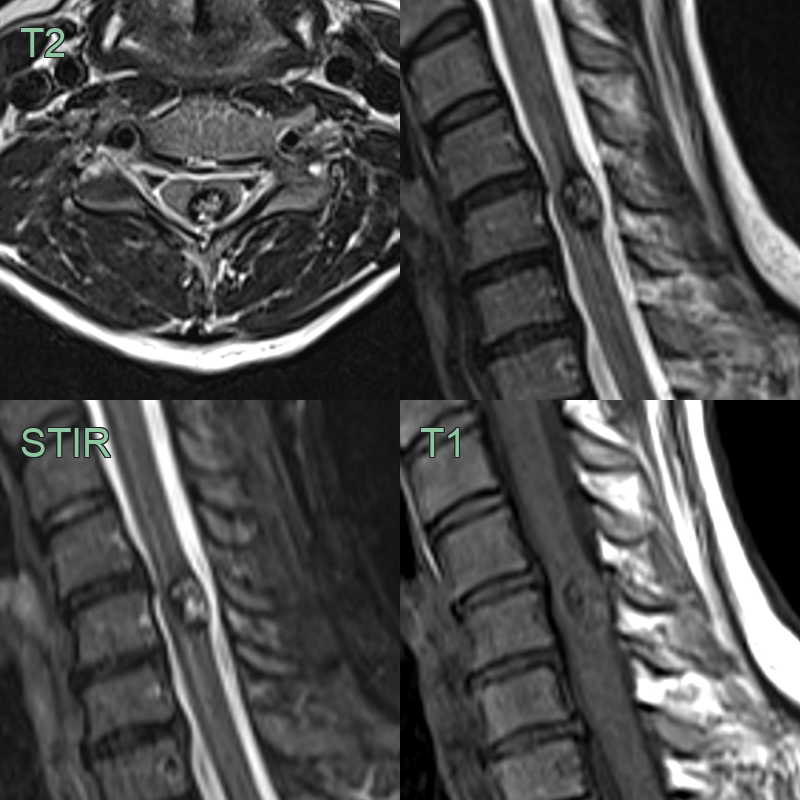

- A 40-year-old patient presented 2 years prior with headache.

- Initial imaging (not shown) showed a hematoma in the left insular region.

- MRI showed many other low intensity lesions within the brain and cervical cord representing cavernomas.

- The T1-shortening within the frontal operculum represented evolving blood product from the hemorrhage at presentation.